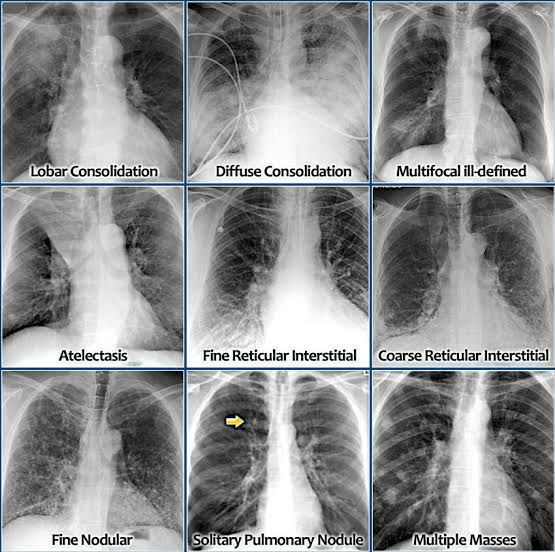

Chest x-rays đŠģ

Chest

Xrrays